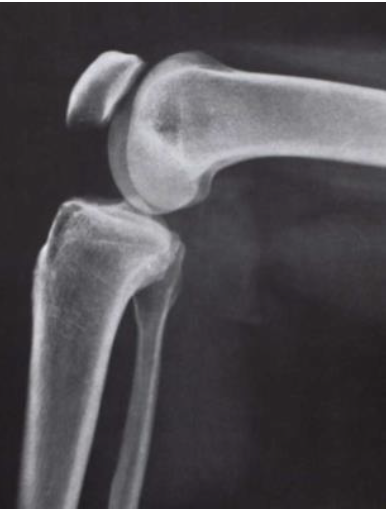

What is this view of the knee? Which views are missing?

Lateral

MISSING:

AP

Intercondylar

Skyline

Medial oblique